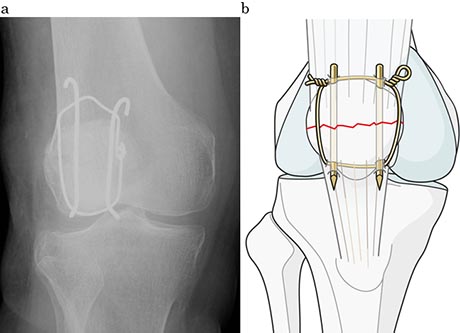

一般に、小さな骨片による骨折が多いので、細い針金や特殊な糸を巻いて固定する方法が良く行われています(図3a, b)。この細い針金や糸を結び付けたり、あるいは、ひまわりの花の様に折れた膝蓋骨の回りを巻いたりすることによって(図4)、膝蓋骨を強く引っ張る力に対抗して、骨折した膝蓋骨が引き裂かれるのを防ぎます。これにより早々に膝の曲げ伸ばしやそのまま歩行することが出来、治療後のリハビリの時間を短縮させる長所を持っています。

図3 細い針金や特殊な糸を巻いて骨のカケラを固定する。

a: 手術方法(テンションバンド固定 https://www.aofoundation.org)

b: 術後X線画像